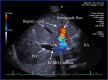

Introduction: Optimal positioning of double lumen bicaval canula for extracorporeal membrane oxygenation (ECMO) support used as a rescue measure in refractory hypoxaemia is essential to facilitate adequate oxygenation, prevent recirculation and avoid complications. Method: Echocardiography via transoesophageal or transthoracic windows can be used as guidance and as a surveillance technique to prevent cannula malposition. We describe a case of Double-Lumen Bicaval VV ECMO cannula malposition leading to a massive retrograde hepatic venous flow. Conclusion: Rapid echocardiographic diagnosis was pivotal in preventing potentially fatal complications.